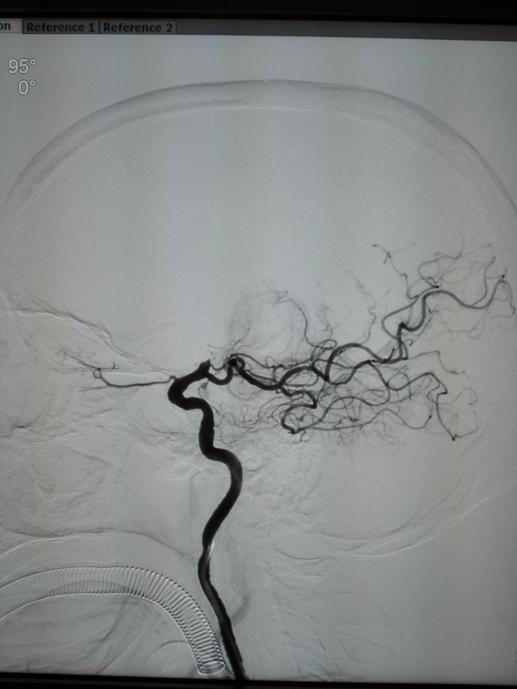

与患者家属沟通后立即于导管室行全脑血管造影术,术中提示右侧颈内动脉末端闭塞,TIMI分级为0分(完全闭塞)。萨仁格日乐主任医师与徐鹏主治医师与患者家属沟通,考虑患者发病特点,行支架取栓术。术中利用取栓支架(Solitaire 4mm×20mm)反复通过闭塞处取栓,前后共五次,最终手术成功,患者闭塞处血运再通。

手术相关图片:

术前正位 术后正位